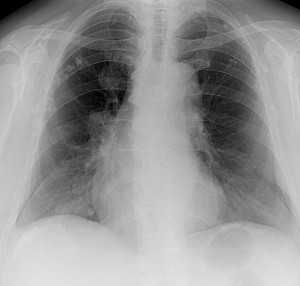

При постановке диагноза мезотелиомы перикарда используются данные рентгенографии грудной клетки, мультиспиральной КТ, магнитно-резонансной томографии сердца, ПЭТ, пункции перикарда с морфологическим исследованием экссудата, торакоскопии. Дополнительно проводятся электрокардиография, эхокардиография, радиоизотопное сканирование сердца.

Рентгенография грудной клетки при мезотелиоме перикарда помогает выявить наличие выпота и его причину - опухоль; КТ и МРТ сердца - оценить наличие и глубину инвазии опухолевого процесса: прорастание злокачественного новообразования в ткани сердца или органы грудной клетки. Большинство мезотелиом ПЭТ-позитивны, поэтому в последнее время для выявления этих опухолей часто применяют ПЭТ сердца с фтордезоксиглюкозой для определения микрометастазов в области перикарда.

Метастазы в легких — фото рентгенограммы. Округлые тени — метастазы рака пищевода. Хорошо виден большой узел округлой формы вблизи переднего отрезка 2-го ребра. На снимке справа - циркулярное сужение пищевода за счет опухолевого утолщения его слизистой оболочки.

Как выглядят метастазы в легких на рентгене? Слева — узловые образования у пациента с раком яичка. Справа - метастазы рака яичников гематогенного характера с выраженным опухолевым лимфангиитом (обратите внимание на деформированный сетчатый, линейный характер легочного рисунка).